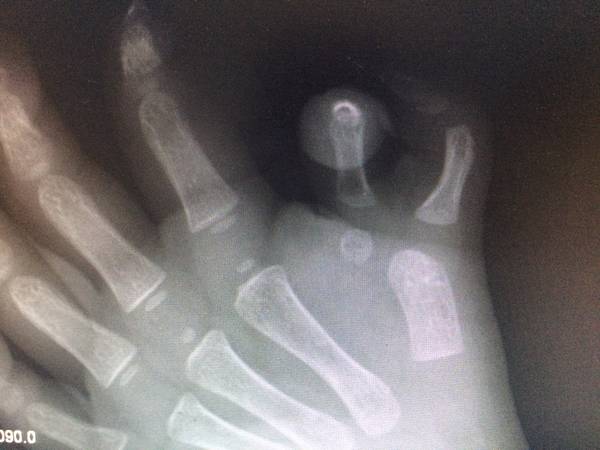

今天做了一台小儿重复拇指畸形患者

按照重庆医科大学附属儿童医院的田晓菲老师和上海九医院王斌教授的指导

进行了部件组装手术

个人觉得手术很成功

微信确实方便,周五收治一名1周岁的重复拇指患儿,入院后拍片发现是VII型多指,手术比预计的复杂多了,而且术后效果不好。幸好有上海九院王斌教授组建的手整形重建外科交流群,小儿先天畸形的国内顶级专家有很多,上海九院王斌教授,上海华山医院的方有生教授,重庆医科大学附属儿童医院的田晓菲教授,还有香港陈德平教授。我把患儿的X线片和手的外观图片发上去后,得到了王斌教授的详细指导,并且发了一组类似的病例图片给我看,告诉我手术注意事项。田晓菲老师更是给出了详尽的分析。昨天晚上夜班,趁孩子睡觉时特意拍照了双手对比的照片,设计了手术方案。今天上午手术按照计划,非常顺利完成了,很为患儿高兴,因为她的手术得到了国内顶级专家的手术指导,相信术后效果应该很好的。交流才会发展,学习才会进步!